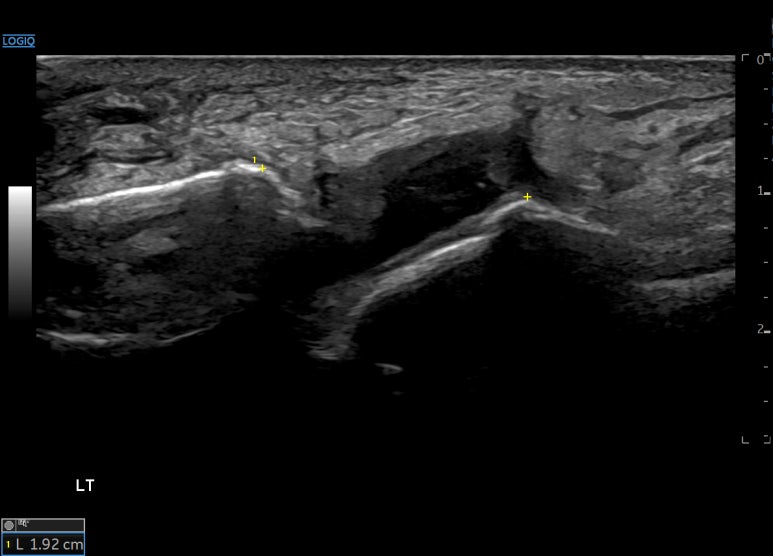

내번 스트레칭할 때

두 뼈 거리는 2.33cm로

4.1mm 벌어집니다.

구허혈에서 확인한

경혈 초음파 소견상

전거비인대가제 기능을 못하는 상태네요.